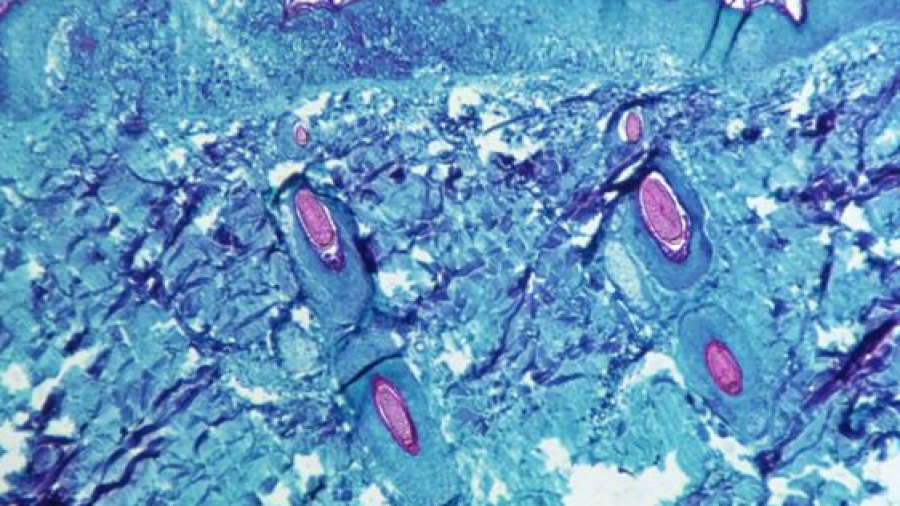

Κρούσματα ευλογιάς των πιθήκων σε παιδιά επιβεβαίωσαν για πρώτη φορά οι αμερικανικές υγειονομικές αρχές, γνωστοποιώντας ότι νοσηλεύονται και είναι καλά στην υγεία τους.

Πρόκειται για ένα νήπιο στην Καλιφόρνια και ένα βρέφος που δεν είναι κάτοικος ΗΠΑ, κρούσματα που δεν σχετίζονται μεταξύ τους και σύμφωνα με τα Κέντρα Ελέγχου και Πρόληψης Ασθενειών (CDC), πρόκειται πιθανότατα για ενδοοικογενειακές λοιμώξεις.

Σημειώνεται ότι η ευλογιά των πιθήκων είναι μια ιογενής λοίμωξη, της οποίας τα συμπτώματα μοιάζουν με τη γρίπη και προκαλεί δερματικά εξανθήματα, ενώ μεταδίδεται κυρίως μέσω στενής επαφής.